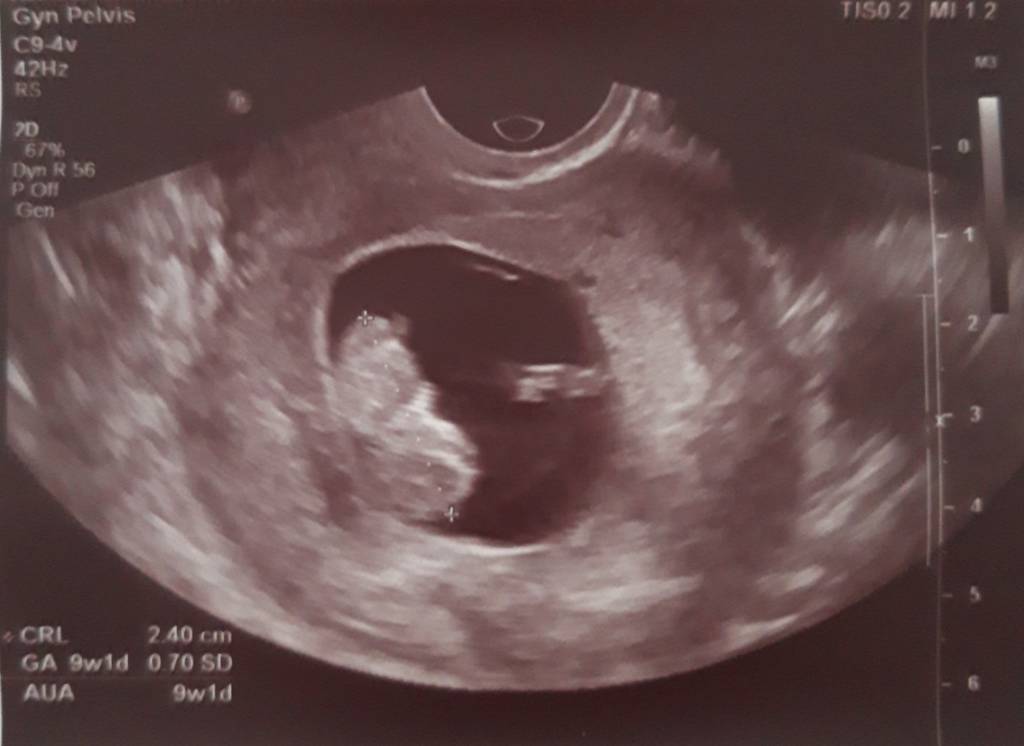

A teraz rośnie bąbelek dziś 9t2d. Wczoraj miałam wizytę u gina termin om zgodny z usg na 20.06.[emoji3] Dzidzia ma 2.40 cm serduszko bije 174bmp.[emoji7]

A i glukoza wyszła mi za dużo bo aż 106 [emoji853]zakaz jedzenia słodyczy owoców, soków masakra tych słodyczy to mogę nie jeść ale nie wiem jak sobie poradzę bez owocy[emoji37][emoji37] w tygodniu powtarzam glukozę i zobaczę co wyjdzie. Oto moja kruszynka.[emoji7] [emoji7] [emoji7]

Zobacz załącznik 917228